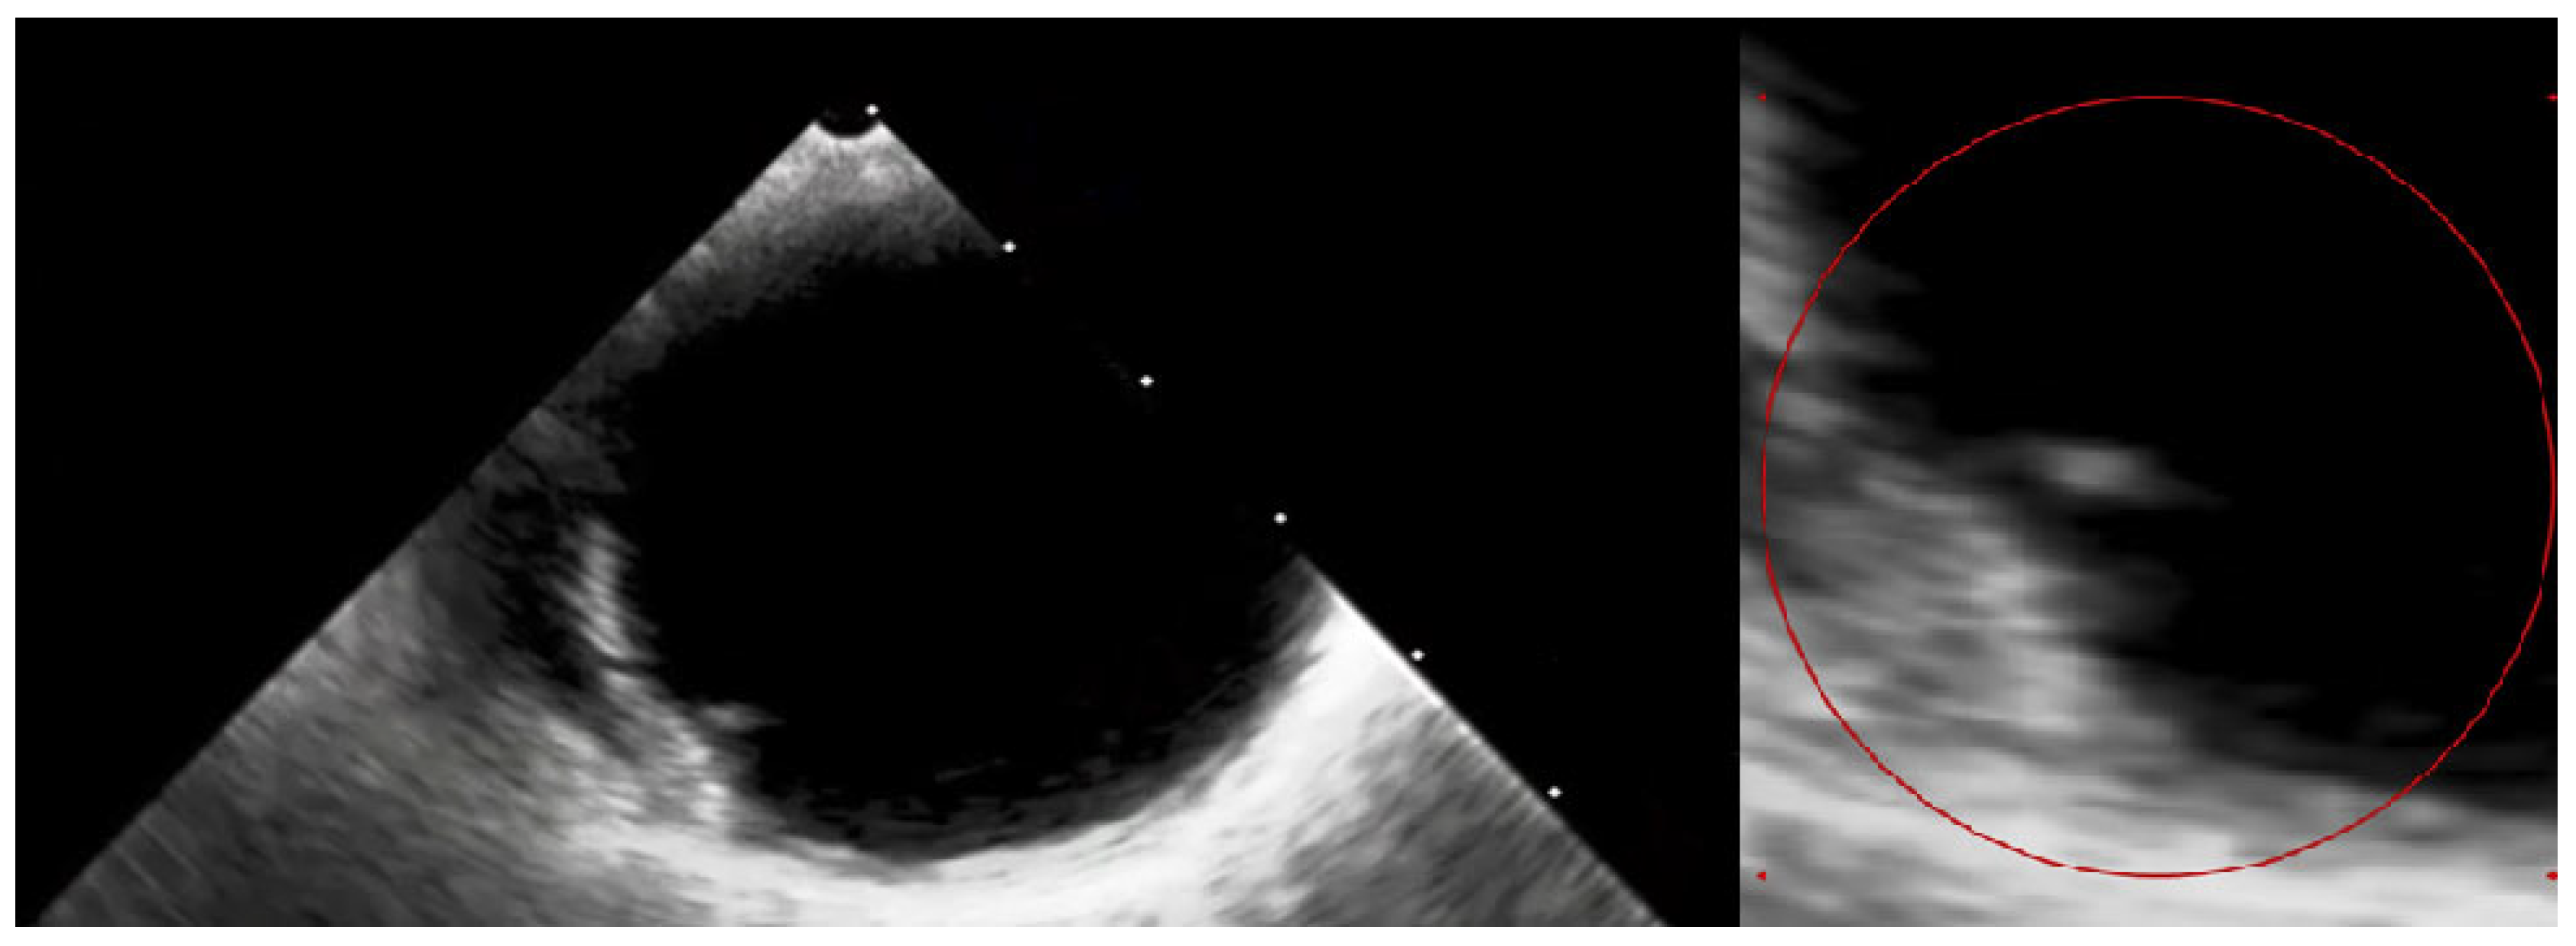

Figure 5.

The transesophageal echocardiography failed to assess the aortic valve due to the artefacts. However, it confirmed the suspicion of the visible ruptured neointima within the aorta on the CT (Video S1—red circle). The patient again consulted with the Heart Team, and the decision about a conservative approach and administration of oral anticoagulation with vitamin K antagonists (VKAs) was sustained. At the 3-month follow-up, the patient was free from angina and syncope, and the control chest CT showed no sign of thrombus presence in the aortic region. The anatomical changes, such as the dimensions and shape of the aortic root, which occurred during TAVI, may have caused the dynamic switch in blood flow through the bioprosthetic valve, thus causing aortic remodelling. This contributes to the fact that the blood stagnates in the prosthetic sinuses, which complements Virchow’s triad and is attributed to thromboembolic events [7]. Furthermore, the ongoing structural bioprosthesis degeneration leading to fibrosis and calcification is often started by leaflet thickening and valve thrombosis [8]. The atherosclerotic plaque in the ascending aorta, or dissection of the neointima along the prosthesis, could also contribute to the thrombotic event. Aortic dissection was reported to be a rare TAVI procedure complication, occurring almost entirely as an acute condition. Regardless, there have been no previous reports of dissection of the neointima in the aortic prosthesis after ViV TAVI [9]. In our case, we suspect that a change in flow through the aorta or mechanical damage during the TAVI could have led to the dissection of the neointima and aortic thrombosis. Additionally, myocardial infarction in patients after TAVI can be the result of co-existing leaflet thrombosis and can cause difficulty in performing PCI procedures due to impaired coronary access [10]. In our case, the patient’s symptoms were most likely associated with the clinical presentation of ViV thrombosis and severe aortic graft thrombosis, in spite of the administration of SAPT—aspirin. The initial treatment with LMWH converted into VKA oral anticoagulants was sufficient to promote thrombus resolution and prevent recurrence at 3-month follow-up.